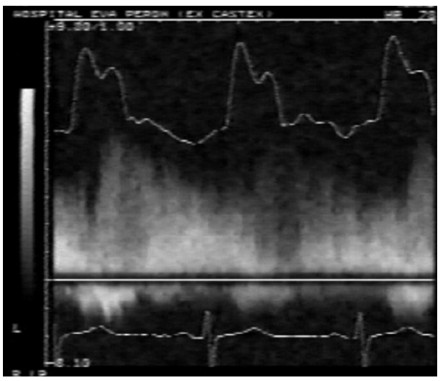

Un paciente de 64 años con antecedentes de tabaquismo, asintomático, es derivado para control por ser portador de estenosis aórtica de grado moderado a grave (Fig. 3). En el examen físico, el choque de punta no estaba desplazado, pero se palpaba un resalto presistólico compatible con onda “a” (aumento de las presiones telediastólicas del ventrículo izquierdo). El pulso carotídeo presentaba un ascenso y amplitud normal. Se auscultaba un cuarto ruido, componente aórtico del segundo ruido conservado y un soplo eyectivo 3/6 en foco aórtico. Frente a la sospecha clínica de miocardiopatía hipertrófica obstructiva, se realiza la maniobra de Valsalva, la cual demostró incremento de la intensidad del soplo. Se repitió el eco-Doppler, que confirmó los hallazgos y dejó como enseñanza que soplo sistólico de estenosis aórtica + pulso carotídeo de ascenso normal = miocardiopatía obstructiva dinámica.

Izquierda: modo M mostrando válvula aórtica con esclerosis y apertura disminuida, sin gradiente por Doppler (parte superior); registro de pulso carotídeo con ascenso rápido y colapso temprano por la obstrucción subaórtica (parte inferior). Derecha: registro en modo M del movimiento anterior sistólico de la válvula mitral (parte superior); gradiente subaórtico telesistólico (parte inferior).